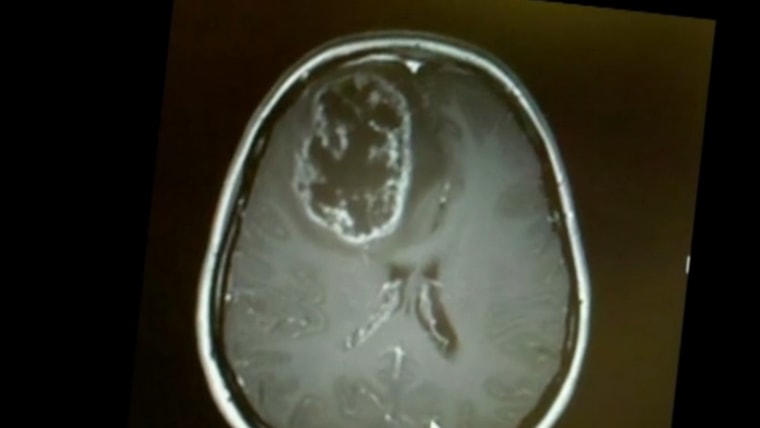

Doctors Cure Women’s Cancer with Polio Injection

A young nursing student in Spartanburg, South Carolina undergoes an experimental treatment to destroy a recurring brain tumor. WYFF’s Mike McCormick Reports.